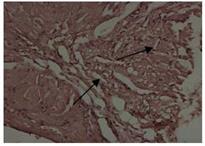

Fig. 2: Effect of MECF treated rat |

Fig. 1-4: Histopathological changes such as myocardial degeneration and inflammation of aorta occurred in rats during high fat diet intoxication and prevention by the treatment with methanolic (500 mg/kg) and ethyl acetate extract (500 mg/kg) of bark of Cassia fistula when compared to the standard Atorvastatin (10 mg/kg). The slides were studied under 200x magnification

Since oxidation of LDL plays a significant role in atherogenesis, amelioration of oxidative stress is equally important as controlling or decreasing hyperlipidemia. When summarized with the above results, the imbalance between oxidative stress generation and antioxidants formation could occur after feeding a high cholesterol diet. Nevertheless, extracts could prevent this pathological process, which indicated its therapeutic and preventive effect on hepatosteatosis induced by high cholesterol diet. Histopathology examination of aorta has shown normal integrity of cell membrane was maintained. Myocardial degeneration and inflammation was decreased in the groups treated with methanolic and ethyl acetate extracts of Cassia fistula when compared to that of cholesterol control group (fig. 1, fig. 2, fig. 3 and fig. 4).

Extracts were capable of potentially decreasing atherogenic Index and have increased the percentage protection. Superoxide dismutase and glutathione peroxidase levels have increased in the groups treated with extracts. Histopathology studies showed that the damage i.e. myocardial degeneration and inflammation that is caused due to atherosclerosis was found to be recovered. Hence it can be concluded that methanolic and ethyl acetate extract of Cassia fistula has antihyperlipidemic and anti-atherosclerotic activity on rats fed on a high cholesterol diet.